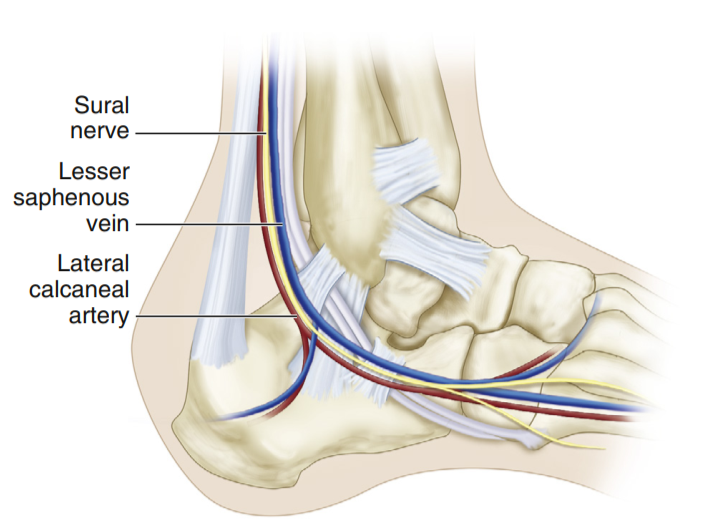

外侧扩大入路的应用解剖

跟骨骨折骨性解剖包括Gissane角Böhler角。在入路中主要注意腓骨长短肌腱、胫后血管及腓肠神经。

在跟骨外侧,需直接切至骨膜表面,将皮瓣全层掀开,避免损伤腓肠神经。皮瓣翻起后,采用克氏针固定于周围骨质,暴露跟骨外侧壁,同时避免损伤皮瓣内神经。